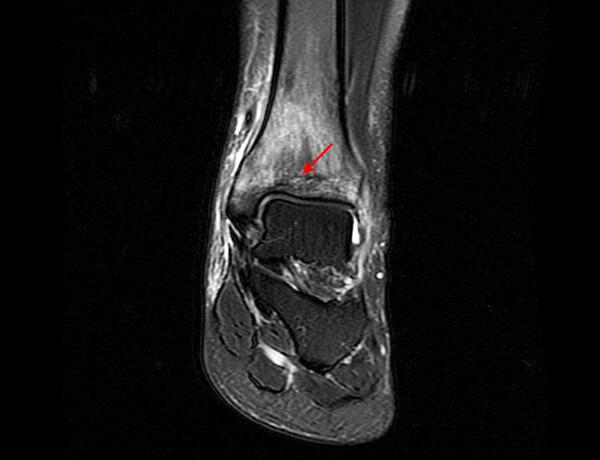

医院医生对他进行了MR检查,结果如下:

看到影像诊断结果和林子洪医生的诊断结果一致,张先生不禁赞叹起威尔医院林医生精湛的医术,他再次来到威尔医院,表示需要林医生的后续治疗。